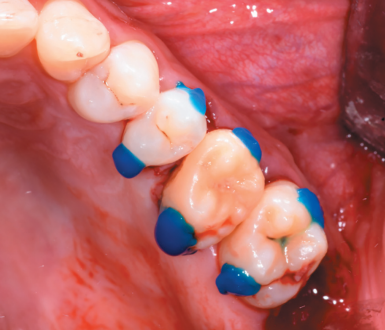

The 2.5, 2.6 and 2.7 teeth were then prepared by etching with orthophosphoric acid at 37% (3M Scotchbond UniversalTM, Minnesota, USA) for 20 seconds (Figure 11). After heavy washing of the etched surface with water, self-etch adhesive (3M Scotchbond UniversalTM, Minnesota, USA) was applied to fix the rigid wire with fluid composite resin (CharismaTM, Kulzer, Hanau, Germany) and conventional composite resin (G-aenialTM, GC, Leuven, Belgium) (Figure 12).

After that, the teeth 2.5, 2.6 and 2.7 were completely insulated by rubber dam, and tooth 2.6 was prepared with orthophosphoric acid and self-etching adhesive, and then cemented the inlay with dual polymerization resin cement (3M Relyx UnicemTM, Minnesota, USA). (Figure 24). After polymerizing for three seconds, the excess cement was removed, finished polymerizing and the rubber dam was removed to adjust the occlusion (Figure 25) and make a verification with a periapical radiograph (Figure 26).